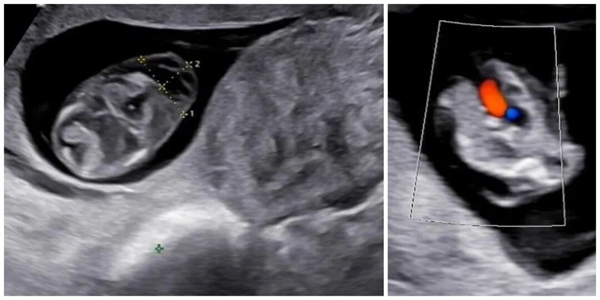

團(tuán)隊(duì)并未就此停止探查,而是繼續(xù)深入檢查胎兒的各個器官結(jié)構(gòu)。當(dāng)觀察到胎兒四腔心切面時,又一個關(guān)鍵異常被發(fā)現(xiàn):僅可見左房室瓣一條前向血流,未見右房室瓣血流通過。這一異常信號直指一種嚴(yán)重的先天性心臟病 —— 胎兒心臟三尖瓣閉鎖!